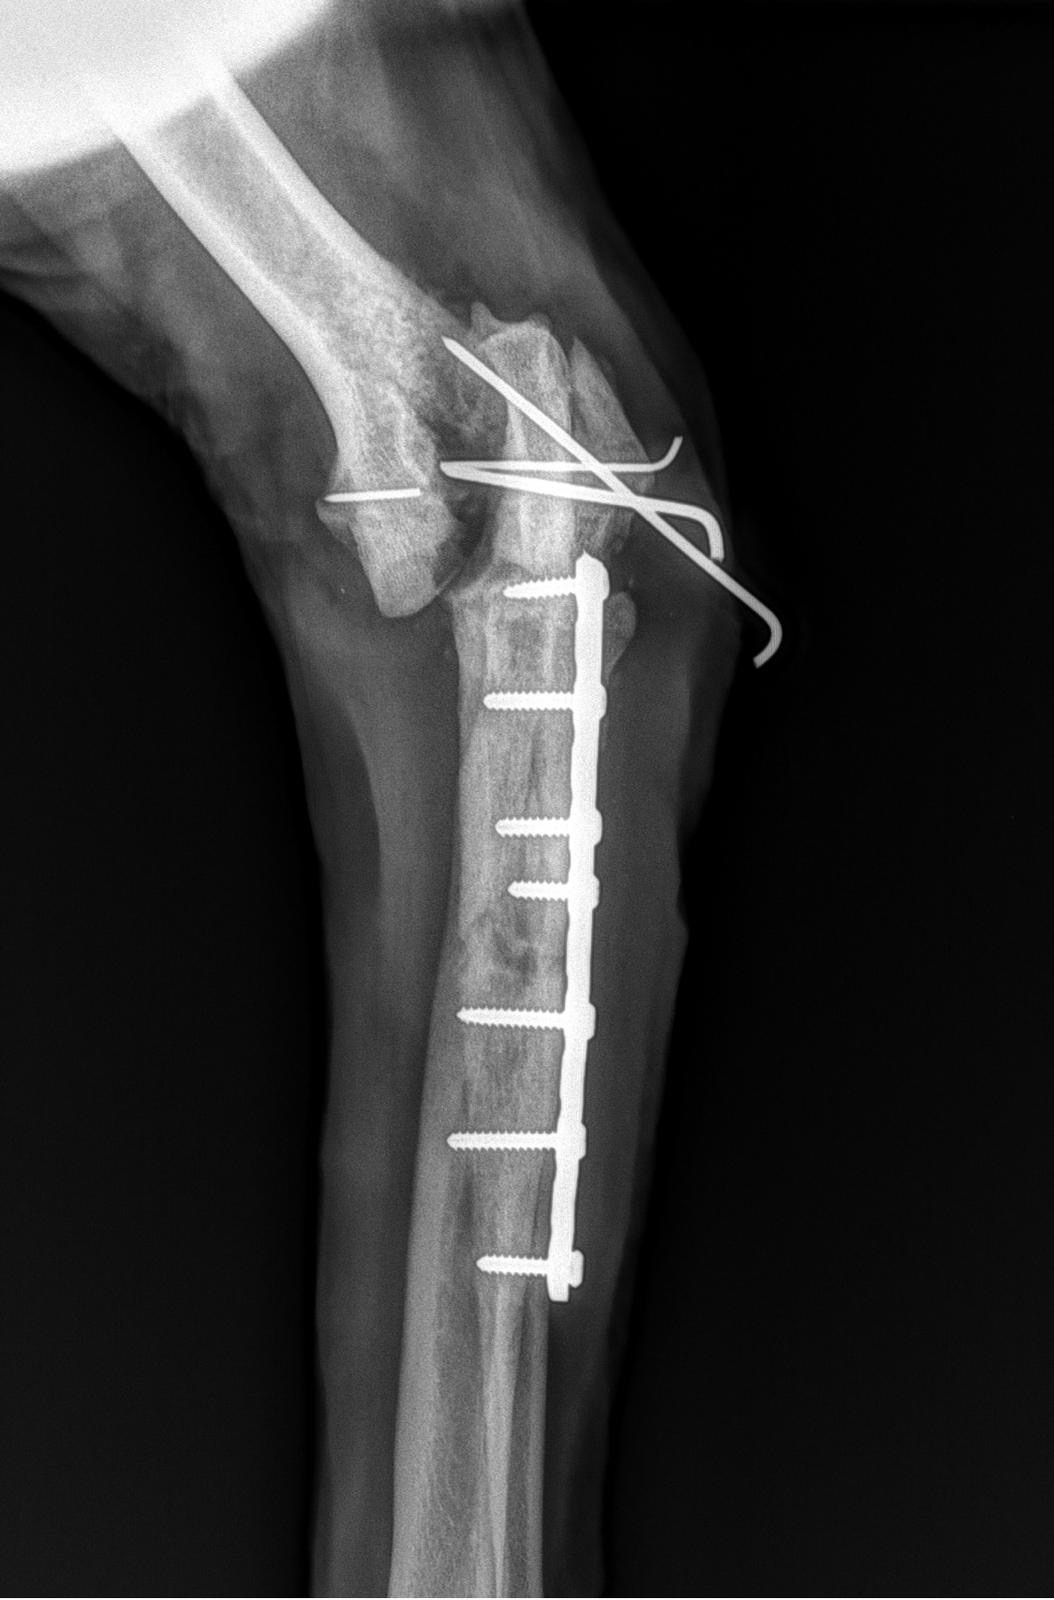

Ende April habe ich mir mein Bein und mein Gelenk am linken Vorderlauf beim Spielen auf dem Feld gebrochen. Es war Freitagnachmittag und wir mussten zur Not Op bis nach Köln fahren, weil es hier in der Umgebung keine Kapazitäten für eine solche Op gab.

Eine Woche nach der Op drangen Drähte durch die Haut aus meinem Gelenk. Für unsere ortsansässige Tierärztin war das nicht typisch, laut Köln aber schon. Also machten wir uns nochmal auf den Weg nach Köln um auf Nummer Sicher zu gehen. Die Oberärztin hat nichtmal den Stützverband abgemacht um sich das Ganze anzuschauen. Lediglich einen Finger unter den Verband gehalten und uns freundlich lächelnd entgegnet: ,,Machen sie sich bitte keine Sorgen, das ist ganz normal.“

Vier Wochen später, Ende Mai, beim Kontrollröntgen wurde dann festgestellt, dass nichts in Ordnung war. Die Drähte haben nicht gehalten und das Gelenk saß nicht dort wo es hingehört. Unsere Tierärztin hat sofort Kontakt zu einer befreundeten Oberärztin (Chirurgin) der Uniklinik Gießen hergestellt. Dort konnte ich schon am nächsten Tag mit einer dicken Schraube re-Operiert werden.

Zu diesem Zeitpunkt war der Knochen im Gelenk aber schon etwas porös. Durch die rausstehenden Drähte der 1. Op sind Keime ins Gelenk eingedrungen. So, dass die neue Schraube im nach hinein auch nicht mehr richtig gehalten hat. In der Uniklinik Gießen haben die Ärzte alles versucht mein Bein zu retten. Weitere Kurznarkosen um das Gelenk immer wieder zu spülen und keimfrei zu bekommen, haben nicht geholfen. Mein Knochen hat immer weiter abgebaut anstatt aufzubauen. Jetzt sehen die Ärzte keine Chance mehr mein Bein zu erhalten.

Ich war ein junger gesunder Hund, der durch eine medizinisch falsche Operationsmethode bei der 1. Op in Köln am Ende sein Bein verliert. An der Uniklinik Gießen sind sich alle Ärzte/Oberärzte (Radiologen/Orthopäden/Chirurgen) einig, die Fraktur im Gelenk wurde in Köln medizinisch falsch rekonstruiert. Dadurch wurden es 3 Monate in denen ich immer schmerzen hatte, fast durchgehend Schmerzmittel und Antibiose bekommen habe, 5 mal sediert war und 24/7 unter Beobachtung stehen musste, damit mir am Ende trotzdem mein Bein amputiert wird.